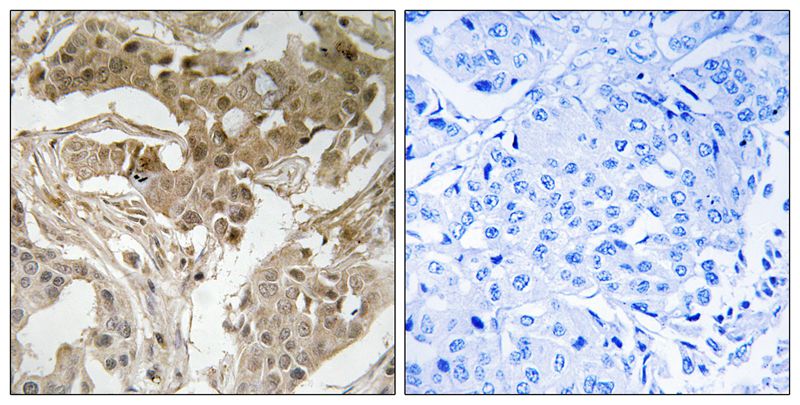

分类: 科研抗体货号: P40430别名: ALK tyrosine kinase receptor; anaplastic lymphoma kinase; anaplastic lymphoma kinase (Ki-1); CD246; EC 2.7.10.1; kinase ALK应用: IHC反应种属: Human